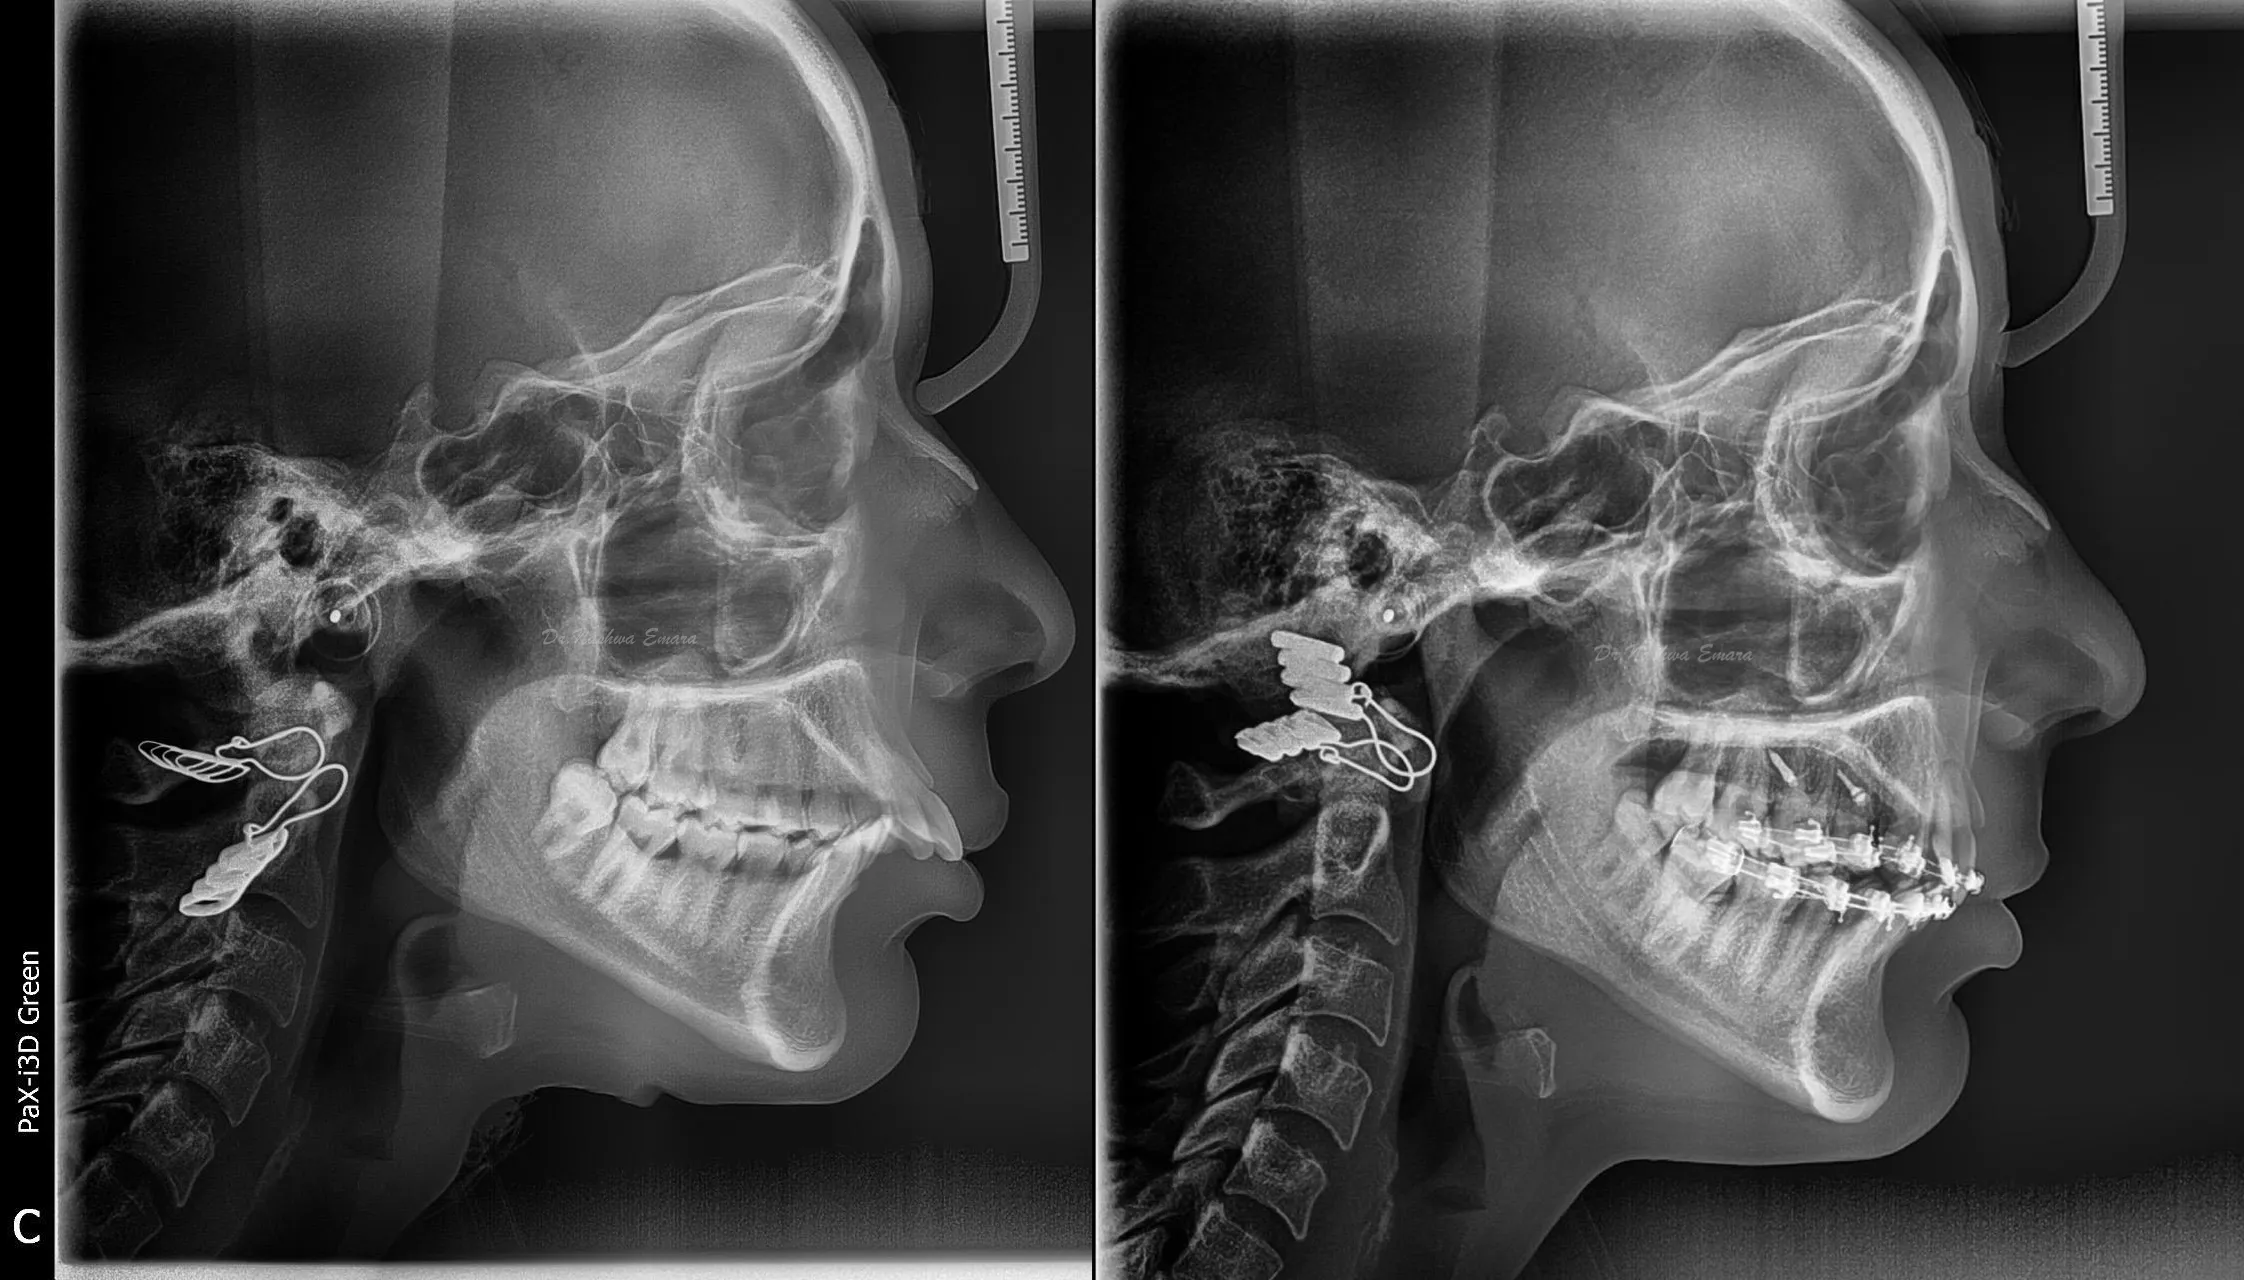

Full Mouth Reconstruction

Orthodontics